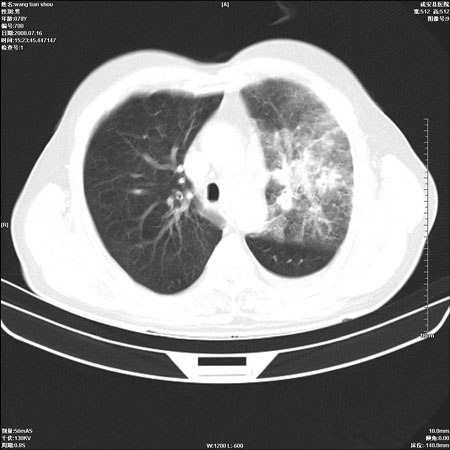

以下是引用qingjing在2008-7-16 19:55:00的发言:[br]1、左上肺不张并堵塞性炎症,建议支气管镜详查;[br]2、左侧胸腔少量积液。

以下是引用wzr在2008-7-16 20:26:00的发言:[br]左肺肺不张伴阻塞性肺炎!另:左侧胸腔少量积液。建议纤支镜检查!